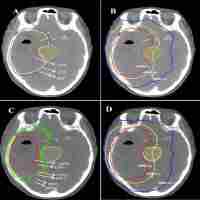

| Abstract | Isocitrate dehydrogenase mutational status defines distinct biologic behavior and clinical outcomes in low-grade gliomas. We sought to determine magnetic resonance imaging characteristics associated with isocitrate dehydrogenase mutational status to evaluate the predictive roles of magnetic resonance imaging features in isocitrate dehydrogenase mutational status and therefore their potential impact on the determination of clinical target volume in radiotherapy. Forty-eight isocitrate dehydrogenase-mutant and 28 isocitrate dehydrogenase–wild-type low-grade gliomas were studied. Isocitrate dehydrogenase mutation was related to more frequency of cortical involvement compared to isocitrate dehydrogenase–wild-type group (34/46 vs 6/24, P = .0001). Peritumoral edema was less frequent in isocitrate dehydrogenase–mutant tumors (32.6% vs 58.3% for isocitrate dehydrogenase–wild-type tumors, P = .0381). Isocitrate dehydrogenase–wild-type tumors were more likely to have a nondefinable border, while isocitrate dehydrogenase–mutant tumors had well-defined borders (66.7% vs 39.1%, P = .0287). Only 8 (17.4%) of 46 of the isocitrate dehydrogenase–mutant tumors demonstrated marked enhancement, while this was 66.7% in isocitrate–wild-type tumors (P < .0001). Choline–creatinine ratio for isocitrate dehydrogenase–wild-type tumors was significantly higher than that for isocitrate dehydrogenase–mutant tumors. In conclusion, frontal location, well-defined border, cortical involvement, less peritumoral edema, lack of enhancement, and low choline–creatinine ratio were predictive for the definition of isocitrate dehydrogenase–mutant low-grade gliomas. Magnetic resonance imaging can provide an advantage in the detection of isocitrate dehydrogenase status indirectly and indicate the need to explore new design for treatment planning in gliomas. Choline–creatinine ratio in magnetic resonance spectroscopy could be a potential more reasonable reference for the new design of delineation of target volume in low-grade gliomas. |